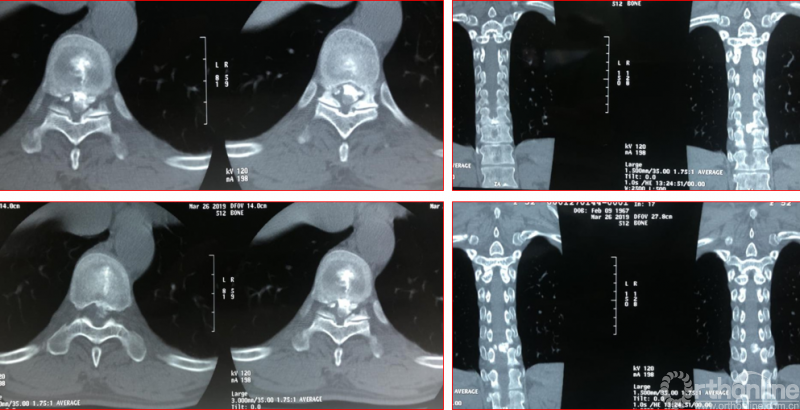

术后影像学资料

术后第二天资料

术后病情评估

术后第二天

JOA评分:8分;RR:37.5%(可);ASIA等级:D级。

术后8个月资料